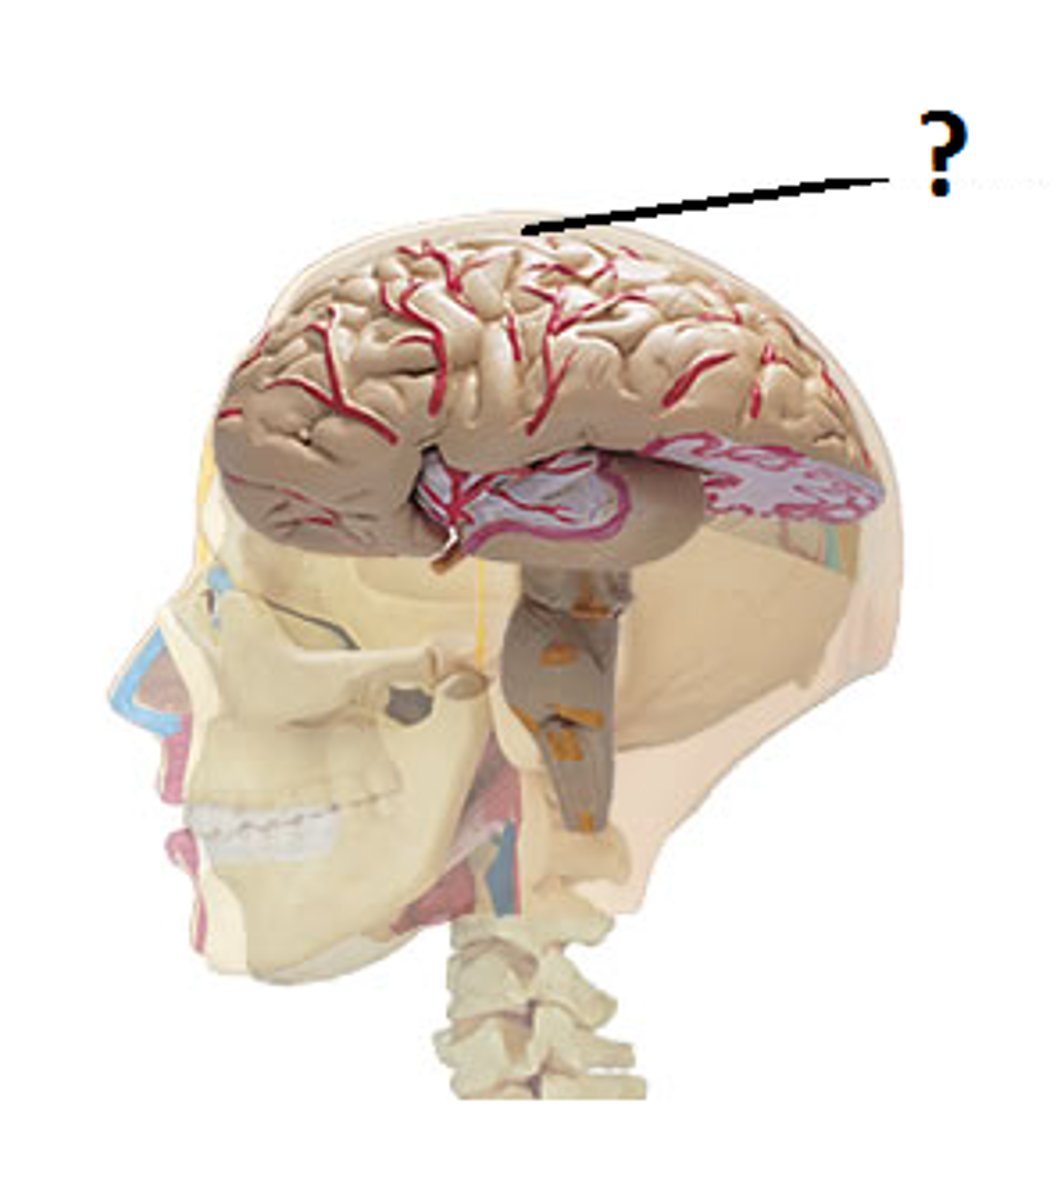

2 important anatomical structures that protect the brain

cranium & meninges

cranium

bony part of brain

meninges

fibrous tissue

3 layers make up the meninges

dura mater, arachnoid mater, pia mater

dura mater

outer periosteal layer & inner meninges layer

periosteal and meningeal

two layers of dura mater

falx celebri

large, sickle-shaped, separates the cerebral hemispheres

tentorium cerebelli

2nd largest, crescent-shaped, separates cerebrum (occipital lobes) from cerebellum (arrow #5)

falx cerebelli

seperates the two hemispheres of the cerebellum. it lies inferior to the tentorium cerebelli, separating cerebellar hemispheres (arrow #7)

diaphragm sellae

smallest infolding covering pituitary gland & sella turcica

arachnoid

middle layer of meninges; weblike appearance that attaches it to deepest layer

arachnoid trabeculae

filaments between the arachnoid and pia mater within the subarachnoid space

superior sagittal sinus

subdural space

space between dura mater and arachnoid mater

subarachnoid space

skin of scalp

arachnoid mater

pia mater

the delicate innermost membrane enveloping the brain and spinal cord.